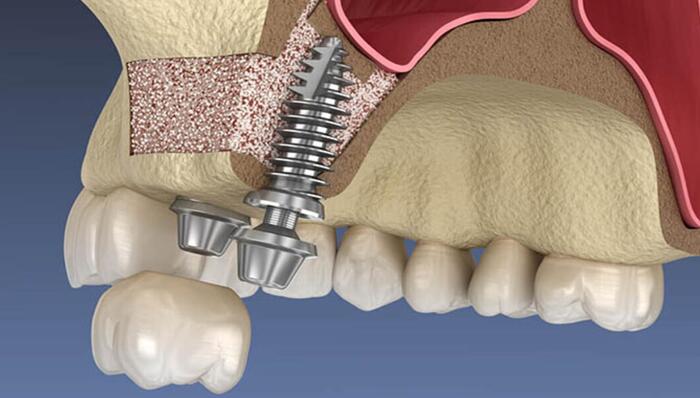

2. Nâng xoang hở

Nâng xoang hở là kĩ thuật nâng xoang bằng cửa sổ bên thành xoang hàm trên, sau đó nâng màng xoang lên và ghép thêm xương tạo đủ chiều cao để đặt trụ Implant. Kỹ thuật này dùng cho trường hợp tiêu xương hàm trên nghiêm trọng, kéo theo thoái hóa xương hàm, xoang hàm mở rộng và tụt sâu xuống phần xương bị tiêu.

Nâng xoang hở chỉ định cho trường hợp thiếu hổng xương nhiều, màng xoang dày, đáy xoang xơ dính, gồ ghề, xoang có dị tật, bị dịch hoặc viêm,… không áp dụng được phương pháp nâng xoang kín.

Quy trình nâng xoang hở được thực hiện như sau:

- Bước 2: Tiến hành gây tê và mở nướu

Sau khi gây tê tại vùng phẫu thuật, bác sĩ tiến hàng mở nướu bằng vết rạch hình tròn hoặc hình vuông bên cạnh răng mất ngoài xoang hàm trên.

- Bước 3: Nâng màng xoang và ghép thêm xương

Dùng kẹp nha khoa tách và nâng nhẹ màng xoang lên, giữ nguyên vị trí. Sau đó, bác sĩ ghép xương bổ sung vào lỗ khoan vùng dưới màng xoang cho đến khi đủ khối lượng yêu cầu.

- Bước 4: Khâu đóng niêm mạc và hẹn ngày cấy trụ

Tiến hành khâu lại nướu và chờ xương tích hợp sau 4 – 6 tháng. Vì nâng xoang hở nên không thể cấy Implant ngay mà phải cần thời gian lành thương. Cuối cùng, bác sĩ hướng dẫn chăm sóc và hẹn ngày đặt trụ phục hình răng.